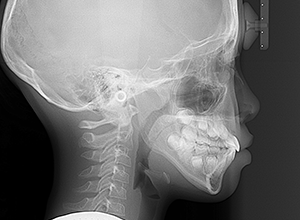

X-Ray

X-Ray所見

セファロ所見 下顎骨体部は大きく下顎枝は前傾しており下顎角は鈍角であった。上顎骨はやや劣位で奥行きがなく下顔面高は高くなっていた。

家族歴や側貌所見、下顎は大きいもののANBは2°でSellaに対して下顎頭は後方に位置していることなどから将来的に重度な下顎前突へ移行することは少ないと予測できた。

パノラマ所見 上顎アーチレングスディスクレパンシー(-)であるが、その他の異常所見は認められなかった。